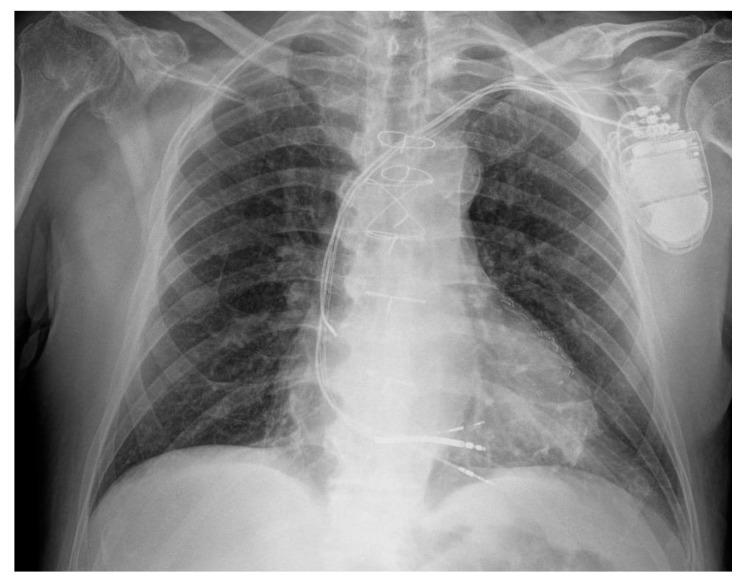

左束支区域起搏时阳极夺获导致的双QRS波群过渡:一例报告

Double QRS Transition Due to Anodal Capture During Left Bundle Branch Area Pacing: A Case Report.

Anodal capture, characterized by a different QRS morphology compared to cathodal capture, is a well-known issue in cardiac resynchronization therapy (CRT). Left bundle branch area pacing (LBBAP), a novel physiological pacing technique, is also used as a bailout strategy following failed conventional CRT implantation. In LBBAP, QRS transition, defined by a change in paced QRS morphology, serves as a key marker of successful lead placement. This case report is the first to document both high-output anodal capture and LBBAP-induced QRS transition in a single individual receiving LBBAP with an implantable cardioverter-defibrillator (ICD) as a bailout strategy for failed cardiac resynchronization therapy with defibrillator (CRT-D) implantation. Their coexistence underscores unique device optimization challenges in this emerging approach.

阳极夺获是心脏再同步治疗(CRT)中一个众所周知的问题,其特征是与阴极夺获相比QRS形态不同。左束支区域起搏(LBBAP)是一种新型的生理性起搏技术,也被用作传统CRT植入失败后的补救策略。在LBBAP中,由起搏QRS形态变化定义的QRS转换是导线成功放置的关键标志。本病例报告首次记录了在一名接受LBBAP并植入植入式心律转复除颤器(ICD)作为心脏再同步除颤治疗(CRT-D)植入失败补救策略的个体中同时出现高输出阳极夺获和LBBAP诱导的QRS转换。它们的共存凸显了这种新兴方法中独特的设备优化挑战。